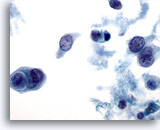

Figure 1

Breast FNA, Fat.

Fat cells, or adipocytes, are large spherical cells with translucent cytoplasm and small eccentric nuclei. They are seen in both benign and malignant aspirates. 40x

Figure 1

Breast FNA, Fat.

Fat cells, or adipocytes, are large spherical cells with translucent cytoplasm and small eccentric nuclei. They are seen in both benign and malignant aspirates.

40x